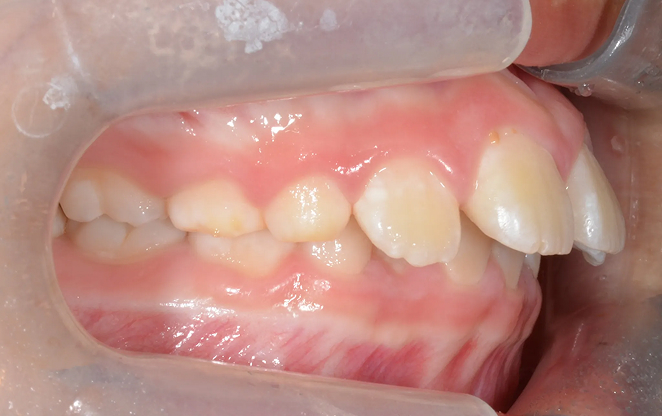

청소년의 자신감을 완성하는

중·고생 2차교정

세상을 향해 첫걸음을 내딛는 아이들을 위한, 조금 더 세심한

교정입니다. 중·고등학생들을 위한 2차 교정은 영구치가 자리를

잡은 후 진행되는 본격적인 교정인데요. 치아의 배열과 교합을

정밀하게 맞추어 성장이 마무리된 치아와 턱이

올바르게 위치할 수 있도록 합니다.